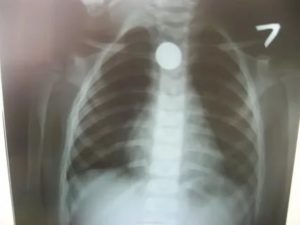

Особую сложность представляют случаи с неорганическими телами, ведь их не видно на стандартном рентген-снимке.

Однако даже тогда можно заметить косвенные признаки: ателектаз, эмфизему и очаговые изменения в легочной ткани.

Рентгенологическое исследование позволяет обнаружить инородное тело, если оно рентгеноконтрастное, косвенные признаки аспирации нерентгеноконтрастного инородного тела (ателектаз, острая эмфизема сегмента, доли или целого легкого), маятникообразное смещение тени средостения при форсированном дыхании (при вдохе тень средостения смещается в сторону поражения, при выдохе — в здоровую сторону).